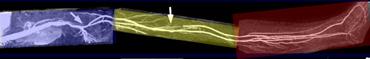

Cách khắc phục hiện tượng ngấm thuốc tĩnh mạch ở cẳng chân

1. Kéo dài cửa sổ động-tĩnh mạch (AV) bằng cách ép tĩnh mạch. Sử dụng băng ép giữa đùi với áp lực 50-60 mmHg. Một băng đo huyết áp thông thường đã tháo bỏ phần kim loại thường hoạt động tốt.

2. Sử dụng lấp đầy không gian k theo kiểu trung tâm nếu có. Nếu thuốc tương phản từ xuất hiện trong tĩnh mạch, điều này sẽ không đóng góp nhiều vào độ tương phản của ảnh vì tại thời điểm đó các đường ngoại vi của không gian k đang được thu nhận, chủ yếu đóng góp vào độ phân giải của ảnh.

3. Ở bệnh nhân thiếu máu cục bộ giai đoạn nặng, thực hiện quy trình chụp hai pha để tập trung trước vào cẳng chân và bàn chân.